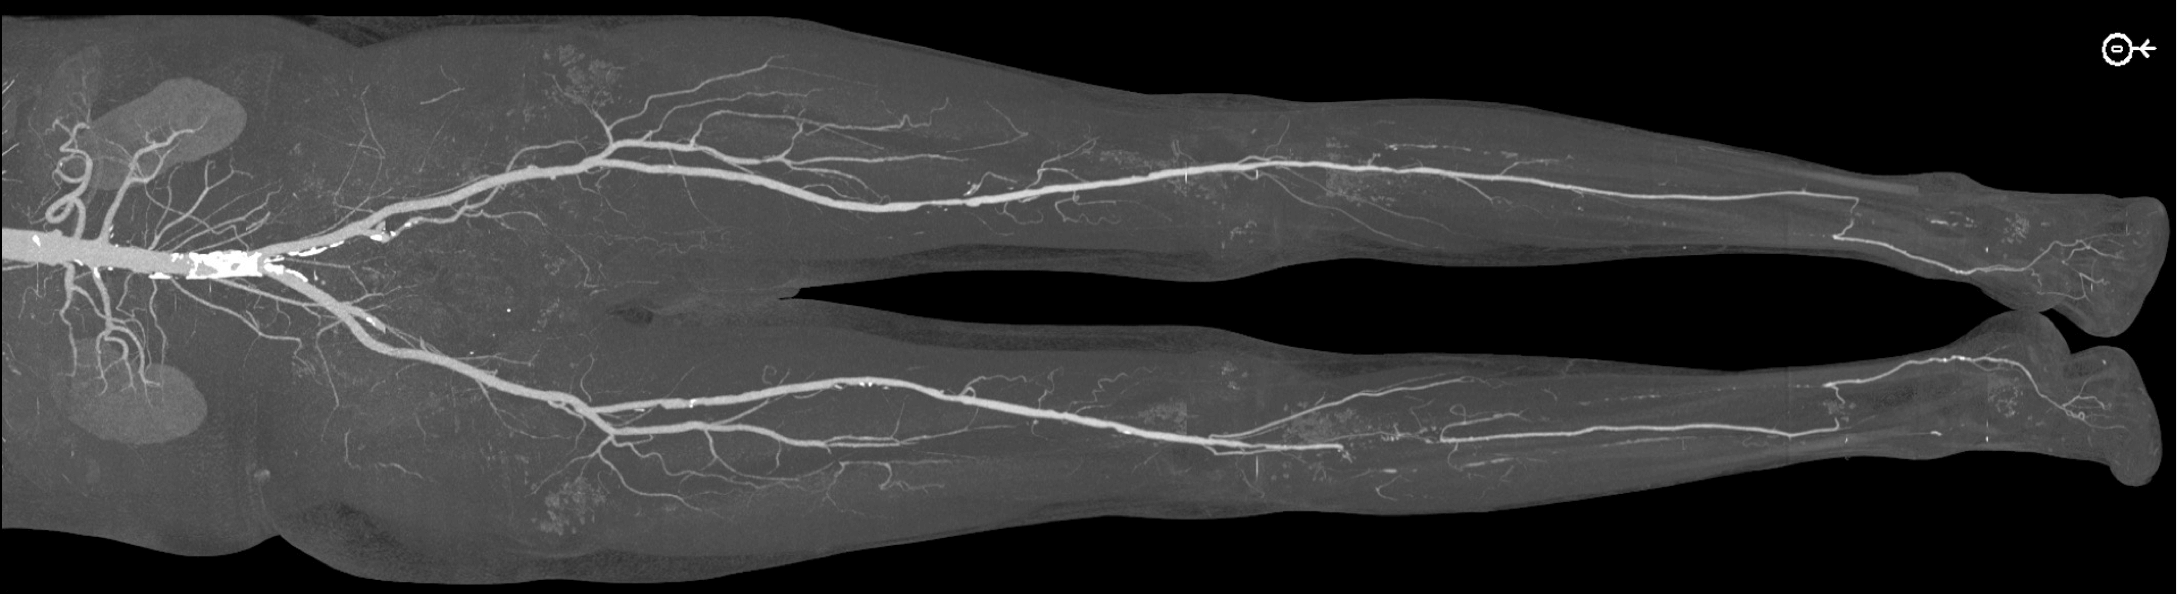

Figure E-G: Left leg.

Figure E. Overview bone-segmented maximum intensity projection (MIP) image shows no significant inflow or femoropopliteal steno-occlusive disease.

Figure F. MIP image of left calf shows occlusion of the posterior and anterior tibial arteries with patent peroneal artery to the distal calf (arrow).

Figure G. Small field of view MIP image shows peroneal reconstitution of the posterior tibial artery, which continues patent across the ankle into the foot. This anatomy is similar to the right side. The reason the patient was more symptomatic on the right is likely related to the absence of the proximal peroneal occlusion on the left side.